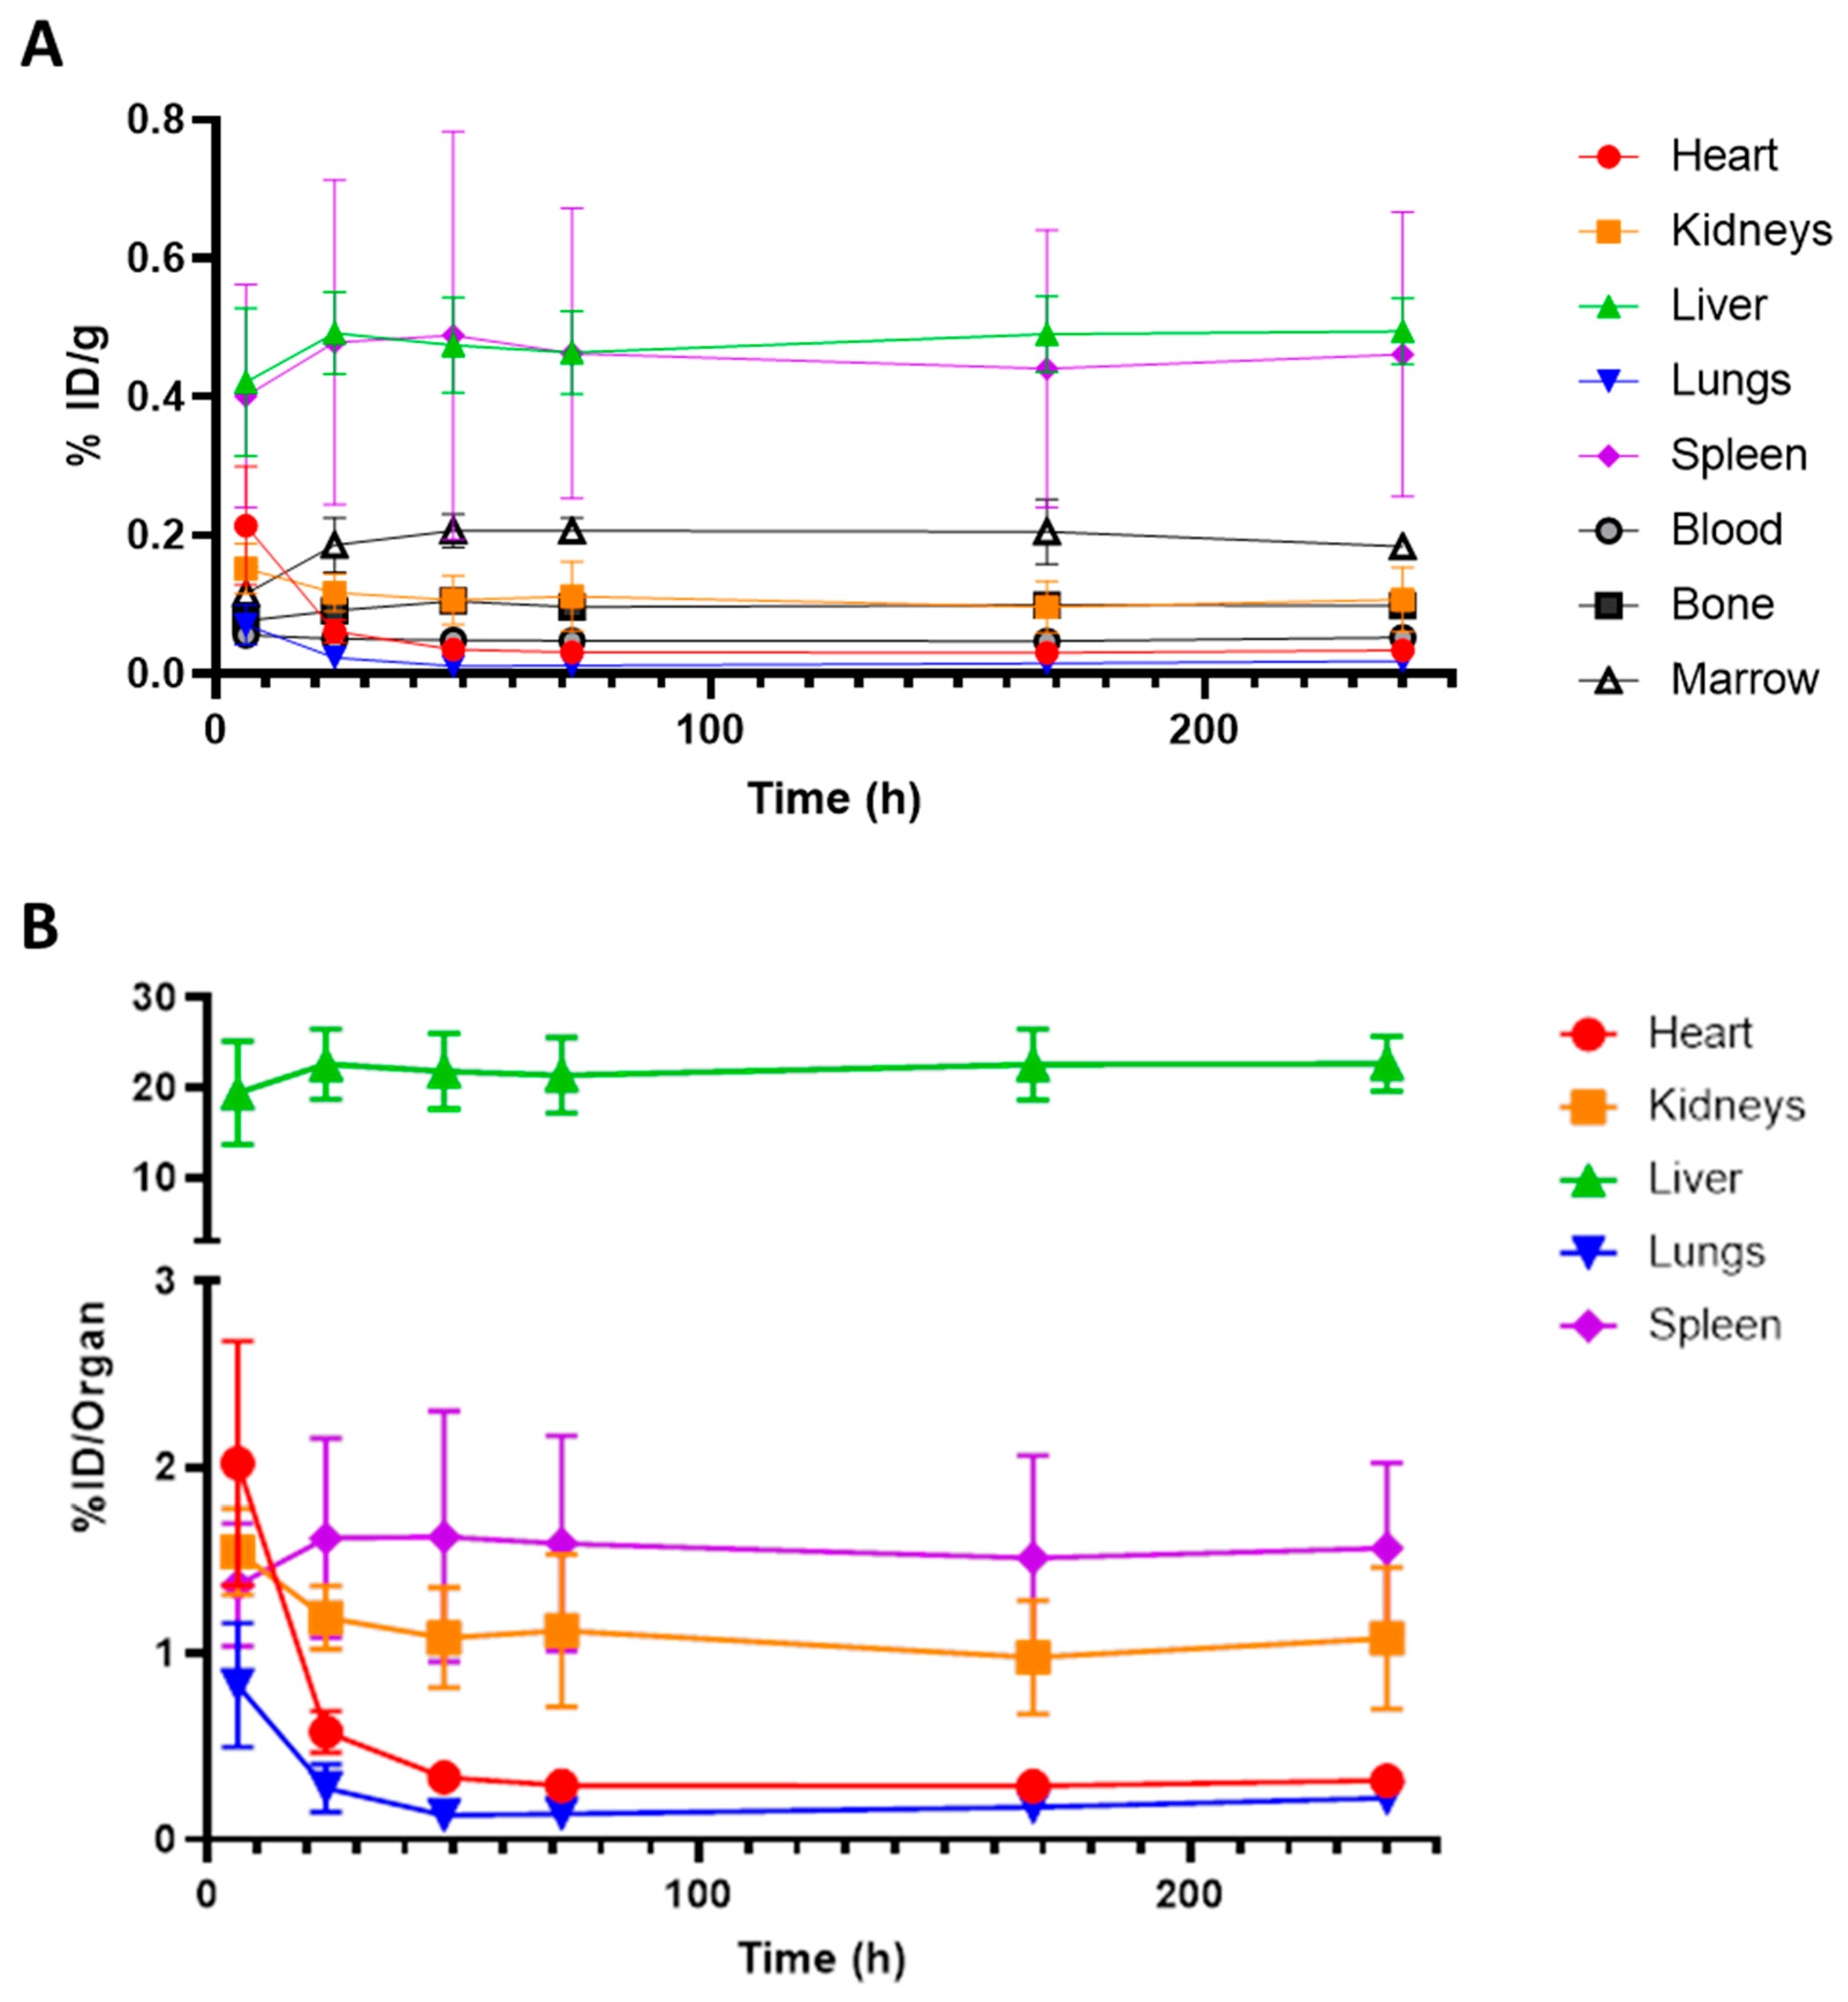

2. Results